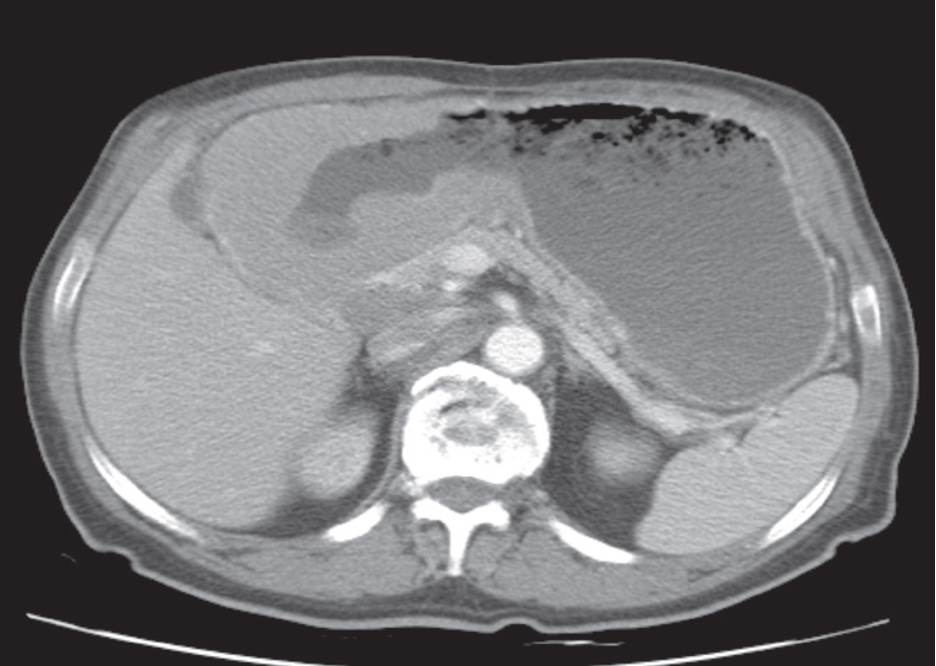

The appearance of primary gastric lymphoma is typically of an extensive area of diffuse thickening of the gastric wall. There may be extensive, bulky lymphadenopathy adjacent to the tumour. The appearance may mimic gastric carcinoma.

Gastric lymphoma in the antrum, demonstrated on CT .

Lymphadenopathy surrounds the inferior vena cava